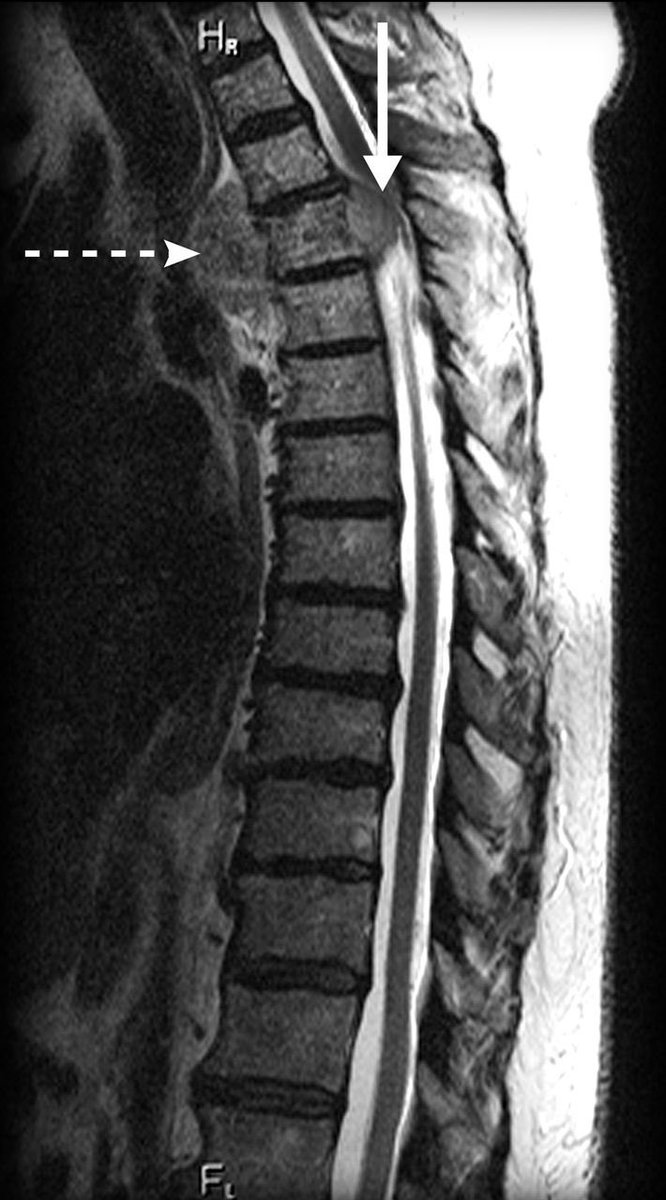

Malignant Spinal Cord Compression (MSCC)- A Thread 🧵

Trust your instincts with this diagnosis Image

Can be the presenting symptom of previously unknown cancer.

Most commonly occurs in patients with a known malignancy (5-10% of all patients)

More common in the following cancers:

-breast

-lung

-melanoma

-prostate

-myeloma

-lymphoma

Can occur with ANY malignancy

Malignant destruction of vertebrae or soft tissue extension through the dural sac leads to ischaemia and compressive disruption of the fragile spinal cord and/or nerves that leave the spinal cord.

Site of compression (approx)

Thoracic region 70%

Lumbosacral 25%

Cervical 5%